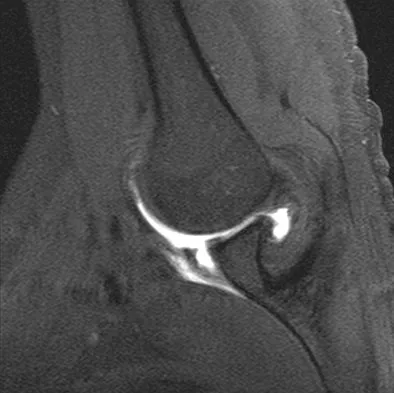

The primary function of structure "A" in Figure 29 is to limit

Explanation

The primary function of the popliteofibular ligament is to resist posterolateral rotation of the tibia on the femur, although it also secondarily resists varus angulation and posterior displacement of the tibia on the femur. The posterior cruciate ligament resists posterior tibial displacement, especially at 90 degrees of flexion. The lateral collateral ligament primarily resists varus displacement at 30 degrees of flexion but also resists posterolateral rotatory displacement with flexion that is less than approximately 50 degrees. The anterior and posterior cruciate ligaments resist varus displacement (along with the lateral collateral ligament) at 0 degrees of flexion. The anterior cruciate ligament primarily resists anterolateral displacement of the tibia on the femur. Sugita T, Amis AA: Anatomic and biomechanical study of the lateral collateral and popliteofibular ligaments. Am J Sports Med 2001;29:466-472.